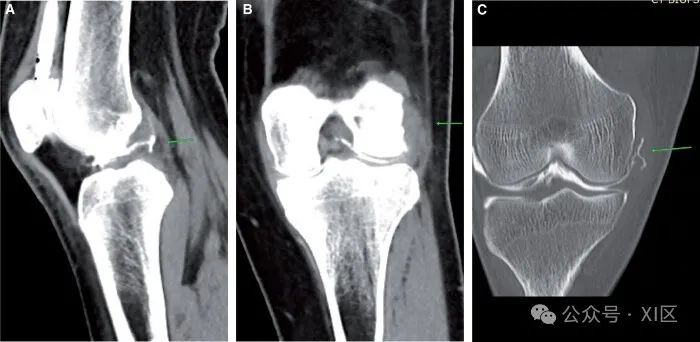

图2 PCL撕裂:(A)关节造影后矢状位图像显示完全PCL撕裂(箭头)。(B) PCL撕脱。骨折和脱位在平片图像上更容易看到。细微的发际线骨折在预先计划的CT图像和手术中的血性抽吸物上更容易看到(图1C)。髌内侧半脱位或脱位的解释大多基于准确的临床病史和在适当的临床背景下髌内侧支持带的增厚。CT关节造影也有助于检测其他发现,如滑车发育不良(图3A-C)。

图3 髌骨半脱位/移位:(A)和(B)轴位图像分别显示软组织窗和骨窗中内侧髌骨支持带增厚(箭头)。(C) 轴位切片显示相关滑车发育不良(箭头)。半月板撕裂的解释与MRI非常相似。在预先计划或手术台上评估中没有其他发现。径向撕裂表现为中部的线性缺陷(图4A)。桶柄状撕裂通常表现为髁间切口中的移位碎片(图4B)。半月板囊肿在关节造影片上可以更好地看到,因为囊肿内充满了造影剂。超声检查发现的半月板旁囊肿在CT关节图上也能更好地评估,CT关节图显示相关半月板撕裂(图4C)。

图4 半月板撕裂:(A)和(B)外侧半月板的径向撕裂(箭头)。(C) 桶柄状撕裂内侧半月板,长箭头指向缩短的半月板,短箭头指向翻转段。(D) 半月板囊肿(长箭头)和相关的水平撕裂(短箭头)。副韧带损伤通常与其他损伤有关。外侧副韧带损伤与膝关节损伤三联征有关。关节造影后图像通常显示造影剂延伸到侧副韧带实质中(图5A和B)。